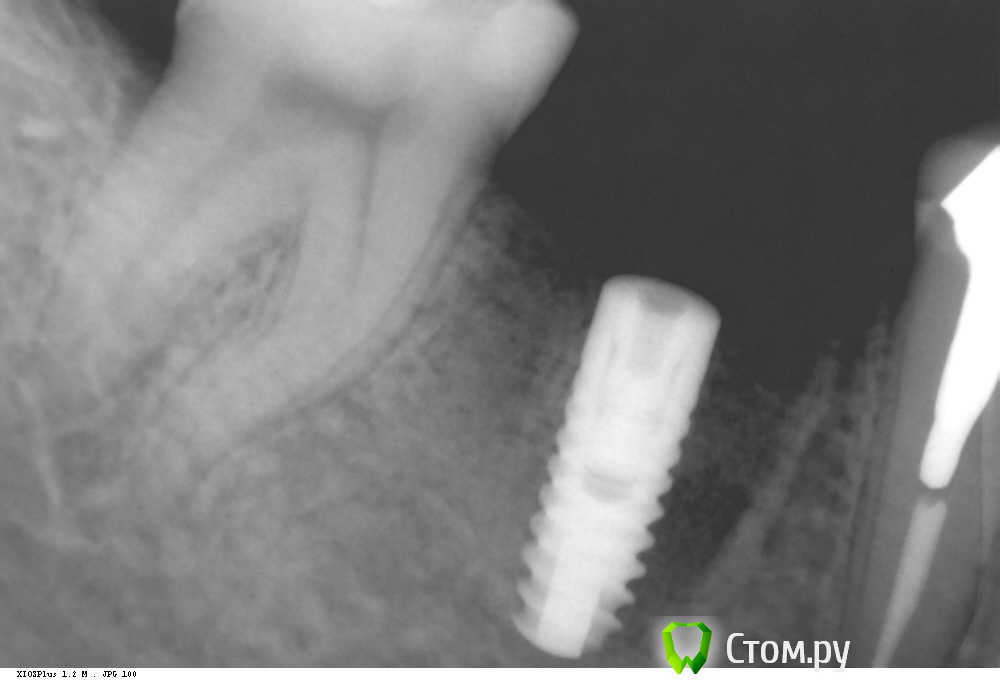

Dr.Sham Опубликовано 8 октября, 2014 Автор Поделиться Опубликовано 8 октября, 2014 IvanK, все стандартно было. не протоколировал.Я не буду ни с кем спорить, меня смущает именно кратер.А про заглубление, вот пример 2 года, полет нормальный. Ссылка на комментарий

Дмитрий Никитюк Опубликовано 8 октября, 2014 Поделиться Опубликовано 8 октября, 2014 Я не буду ни с кем спорить, меня смущает именно кратер. А про заглубление, вот пример 2 года, полет нормальный.Полёт мог быть отличным, если бы мы видели кость на плечах имплантатов… Вы можете сильно обжечься при тонком биотипе, если не будете ставить глубже. Но это Ваше дело, учиться на чужих ошибках или на своих. 2 Ссылка на комментарий

Dr.Sham Опубликовано 8 октября, 2014 Автор Поделиться Опубликовано 8 октября, 2014 Полёт мог быть отличным, если бы мы видели кость на плечах имплантатов…Вы можете сильно обжечься при тонком биотипе, если не будете ставить глубже. Но это Ваше дело, учиться на чужих ошибках или на своих.Дмитрий, вы меня ине поняли. Я не спорю ни в коем случае про заглубление, что это нужно на анкилосе, я хотел показать как раз-таки то, что на последнем снимке тоже не заглубил, кость ушла, но кратера нет. Ссылка на комментарий